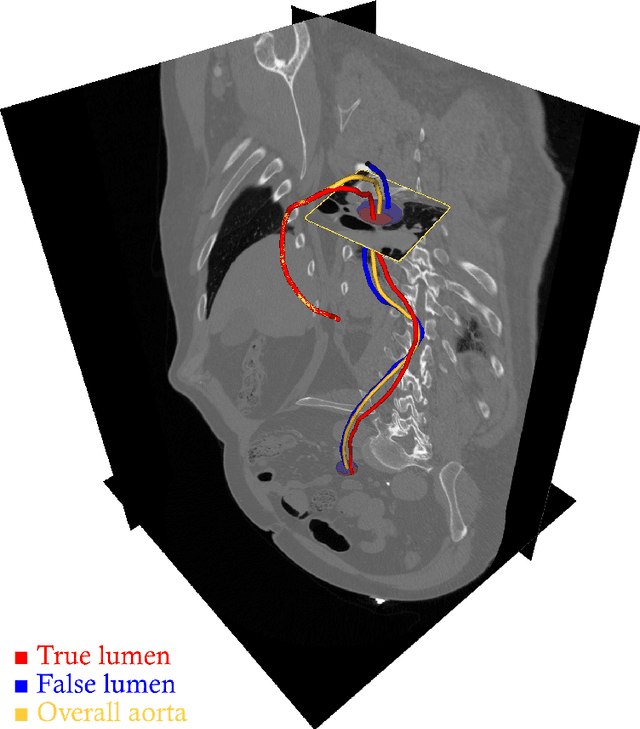

Abstract:The aortic vessel tree is composed of the aorta and its branching arteries, and plays a key role in supplying the whole body with blood. Aortic diseases, like aneurysms or dissections, can lead to an aortic rupture, whose treatment with open surgery is highly risky. Therefore, patients commonly undergo drug treatment under constant monitoring, which requires regular inspections of the vessels through imaging. The standard imaging modality for diagnosis and monitoring is computed tomography (CT), which can provide a detailed picture of the aorta and its branching vessels if combined with a contrast agent, resulting in a CT angiography (CTA). Optimally, the whole aortic vessel tree geometry from consecutive CTAs, are overlaid and compared. This allows to not only detect changes in the aorta, but also more peripheral vessel tree changes, caused by the primary pathology or newly developed. When performed manually, this reconstruction requires slice by slice contouring, which could easily take a whole day for a single aortic vessel tree and, hence, is not feasible in clinical practice. Automatic or semi-automatic vessel tree segmentation algorithms, on the other hand, can complete this task in a fraction of the manual execution time and run in parallel to the clinical routine of the clinicians. In this paper, we systematically review computing techniques for the automatic and semi-automatic segmentation of the aortic vessel tree. The review concludes with an in-depth discussion on how close these state-of-the-art approaches are to an application in clinical practice and how active this research field is, taking into account the number of publications, datasets and challenges.